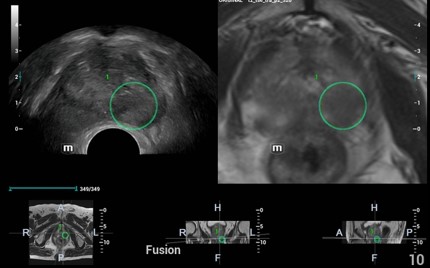

iFusion* prostaty

Fúzia UZV obrazu s CT alebo MRI zobrazením. Citlivejší magnetický snímač pohybu s milimetrovou presnosťou. Vďaka CT/MR navigácie poskytuje presnú lokalizáciu nádoru ako aj lepšie vedenie intervencie.